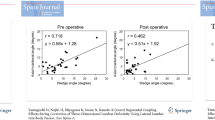

During flexion, extension, lateral bending, and axial rotation, the maximum IDP values in the TLIF model were 0.34 MPa, 0.27 MPa, 0.27 MPa, and 0.32 MPa at the L1/2 segment, respectively; 0.31 MPa, 0.26 MPa, 0.27 MPa, and 0.29 MPa at the L2/3 segment, respectively; 0.28 MPa, 0.21 MPa, 0.22 MPa, and 0.23 MPa at the L3/4 segment, respectively; and 0.23 MPa, 0.20 MPa, 0.20 MPa, and 0.20 MPa at the L5/S1 segment, respectively. Compared with the intact model, the maximum IDP of the TLIF model increased by 0.7-6.8% at the L1/2 segment, 0.8-6.8% at the L2/3 segment, 0.1-6.6% at the L3/4 segment, and 0.5-6.4% at the L5/S1 segment (Fig. 5A). With the increase in total L1-S1 ROMs, the IDP of each adjacent segment increased in all motion directions (Fig. 5B). The relationship between IDP and total L1-S1 ROM was synthesized into continuous function.

FJF

During flexion, the FJF values of each segment were not obtained because the facet joints were not in contact. For lateral bending, the FJF values of the L1/2 and L5/S1 segments were not measured. In addition, the maximum FJF values of the intact model and TLIF model at the L2/3 segment (18.43 N vs. 18.52 N) and L3/4 segment (5.57 N vs. 5.68 N) were similar during lateral bending. During extension and axial rotation, the maximum FJF values in the TLIF model were 42.59 and 108.25 N at the L1/2 segment, respectively; 109.66 and 117.84 N at the L2/3 segment, respectively; 54.42 and 155.00 N at the L3/4 segment, respectively; and 7.46 and 110.21 N at the L5/S1 segment, respectively. Compared with the intact model, the maximum FJF of the TLIF model during extension and axial rotation increased by 85.2-134.2% at the L1/2 segment, 36.4-50.7% at the L2/3 segment, 35.5-46.5% at the L3/4 segment, and 62.8% at the L5/S1 segment (Fig. 6A). With the increase in total L1-S1 ROMs, the FJF of each adjacent segment increased (Fig. 6B). The relationship between FJF and total L1-S1 ROM was synthesized into continuous function.

Relative total L1-S1 ROMs after L4/5 TLIF

The total L1-S1 ROM with IDP or FJF constraint in the TLIF model was calculated using the fitting functions when the IDP or FJF value in the TLIF model was the same as the maximum IDP or FJF value in the intact model. The total L1-S1 ROMs with IDP and FJF constraints in each segment and direction were shown in Fig. 7A-B. The relative total L1-S1 ROM was determined as the minimum total L1-S1 ROMs with IDP and FJF constraints in all adjacent segments. As a result, the relative total L1-S1 ROMs were 11.03°, 12.50°, 12.14°, and 9.82° in flexion, extension, lateral bending, and axial rotation, respectively. Compared with the intact model, the relative total L1-S1 ROMs of the TLIF model decreased by 29.3%, 25.5%, 19.6%, and 19.9% in flexion, extension, lateral bending, and axial rotation, respectively (Fig. 7C).

Determination of a relative total lumbar ROM. (A) The total L1-S1 ROM with IDP constraints. (B) The total L1-S1 ROM with FJF constraints. (C) The relative total L1-S1 ROM in the TLIF model. ROM: range of motion; IDP: intradiscal pressure; FJF: facet joint force; TLIF: transforaminal lumbar interbody fusion